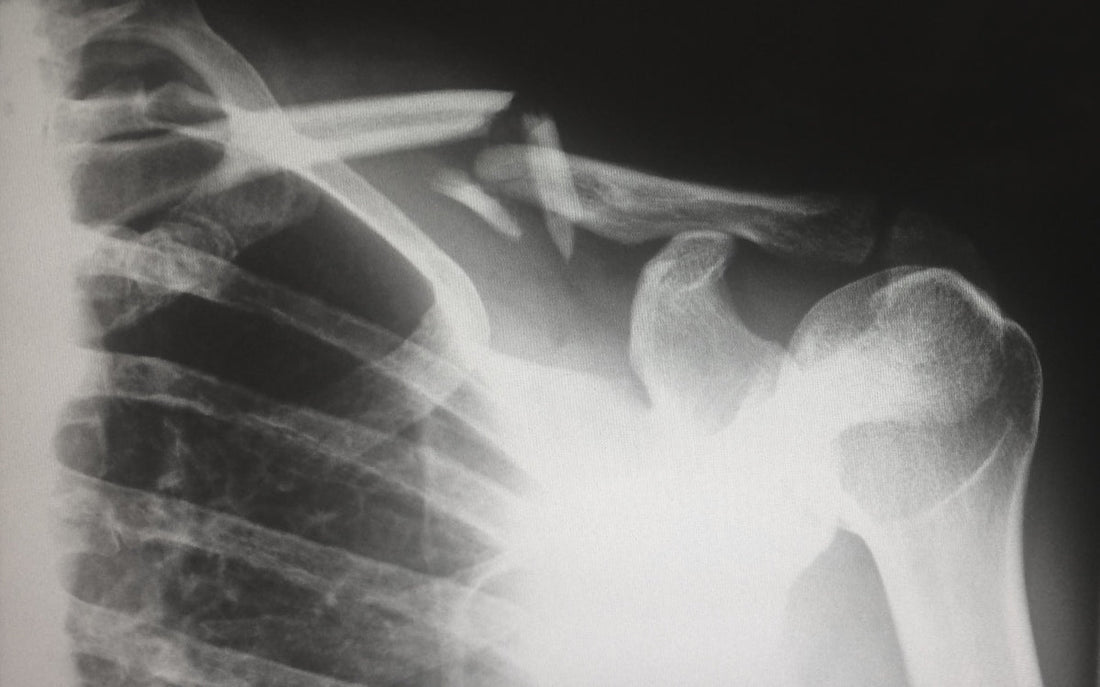

Osteogenesis Imperfecta, often referred to as brittle bone disease, is a genetic disorder characterized by fragile bones that break easily, often with little or no apparent cause. This condition comes in several types, ranging from mild forms to more severe manifestations that can significantly affect an individual's lifestyle and mobility.

OI is caused by mutations in the genes that are responsible for producing collagen, a primary protein in bone tissue that provides strength and structure. The most common signs of Osteogenesis Imperfecta include frequent bone fractures, bluish sclera (the white part of the eyes), hearing loss, poor teeth development, and joint laxity. In severe cases, individuals may experience stunted growth or have abnormal skull shape and face specific challenges regarding mobility and independence.